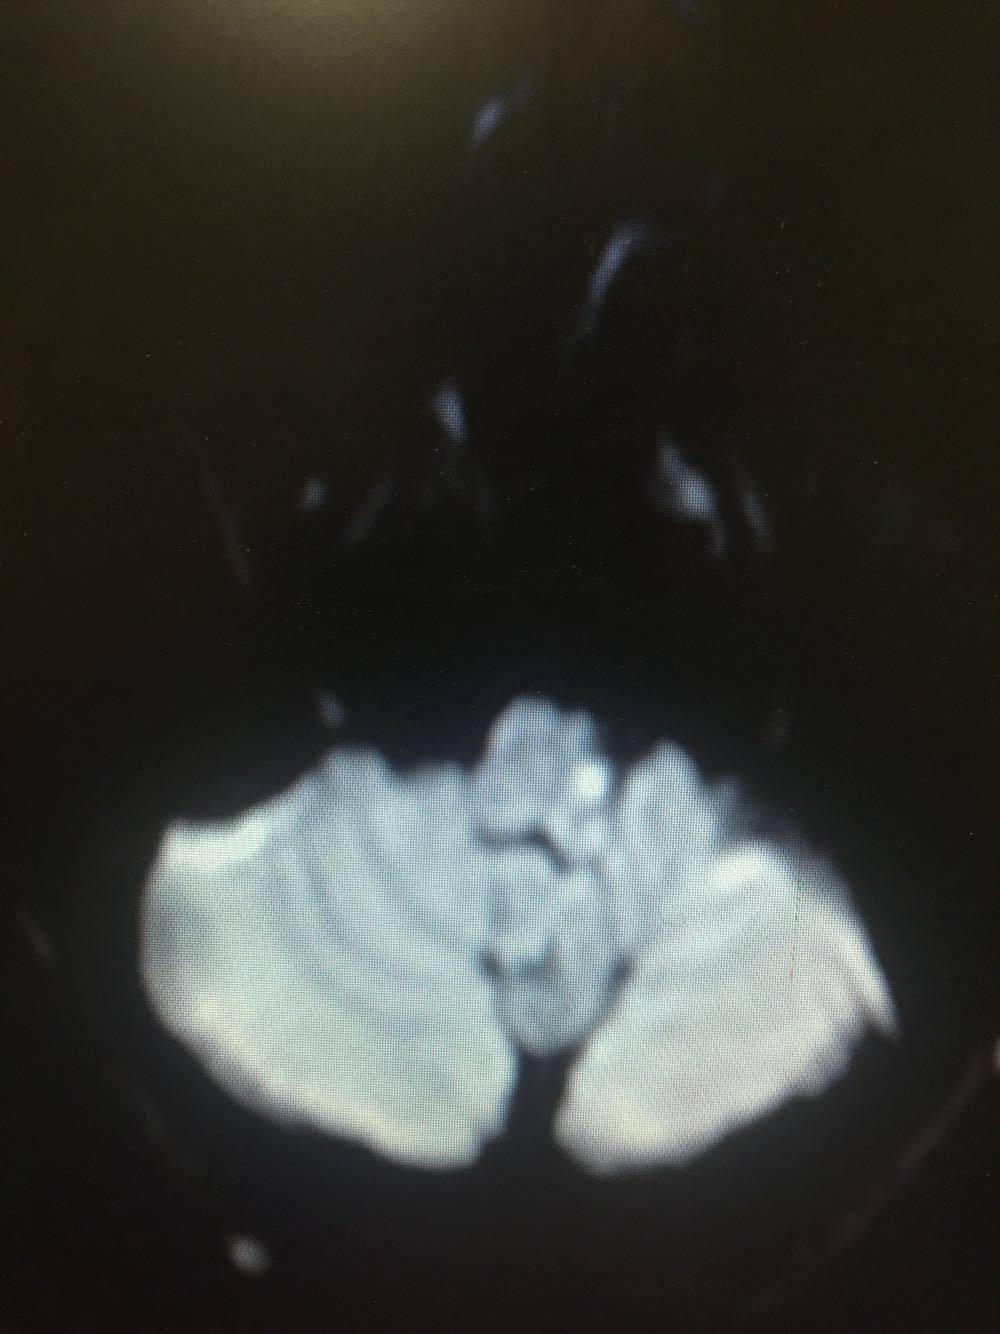

延髓梗死

延髓梗死、高血压、高脂血症 治疗改善循环、抗血小板聚集、脑保护、营养神经、调控血压、血脂对症治疗

患者存在中枢性嗝逆顽固,给予胃复安等治疗,治疗效果不佳。